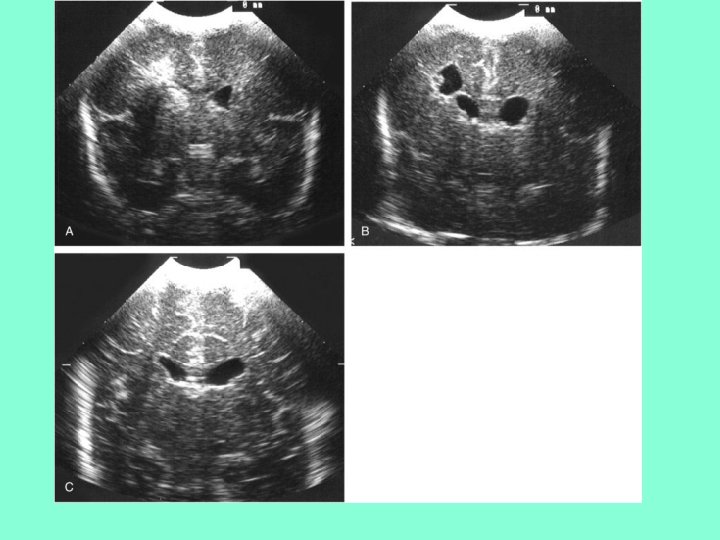

Классификация ПВЛМ From De. Vries L et al: The spectrum of leukomalacia using cranial ultrasound. Behav Brain Res 49: 1, 1992. • 1 степень – транзиторное перивентрикулярное увеличение эхоплотности в первые 7 дней жизни • 2 степени –локальные лобно-височные кисты • 3 степени - распространенные перивентрикулярные кисты • 4 степень – распространенные перивентрикулярные и субкортикальные кисты

• А – нормальный ребенок в 31 неделю ГВ • В и С - бивентрикулярные кисты